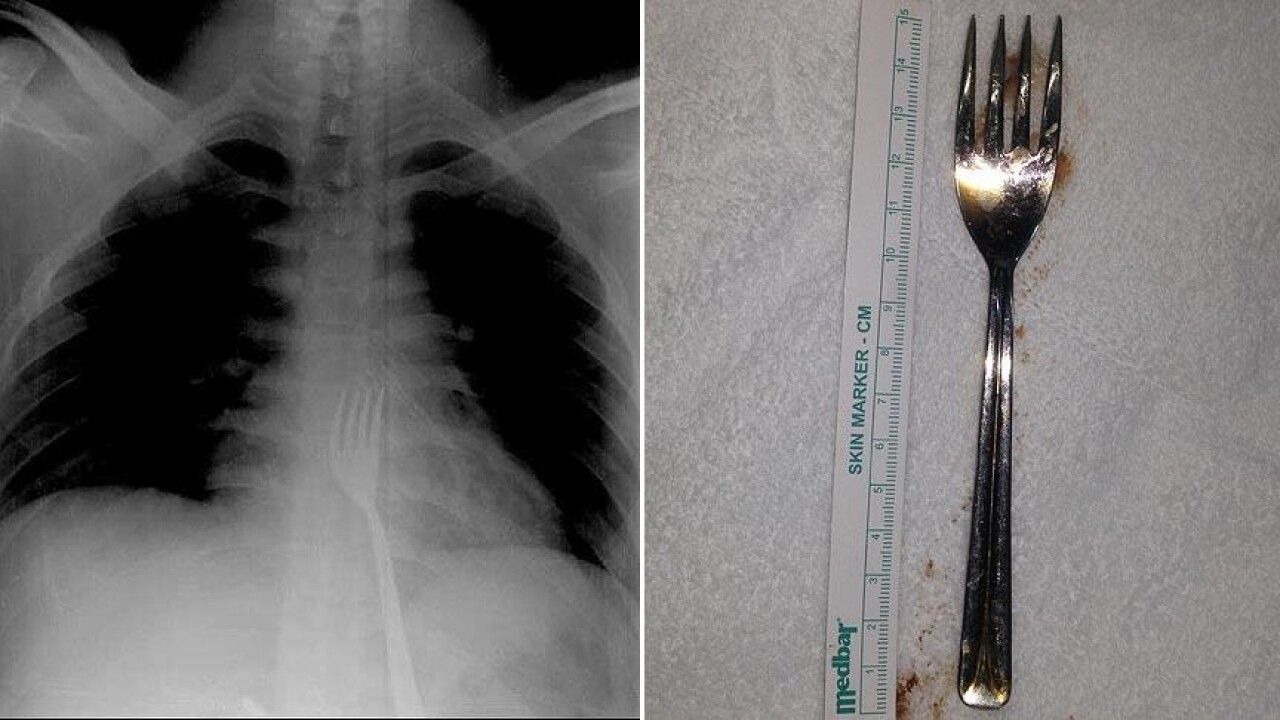

ADÜ Tıp Fakültesi Göğüs Cerrahisi Ana Bilim Dalı Öğretim Üyesi Dr. Salih Çokpınar ve Genel Cerrahi Ana Bilim Dalı Dr. Öğretim Üyesi Akay Edizsoy koordinasyonundaki operasyonla midede kesi açılarak çatal çıkarıldı.

"Biz en çok bu yüzden tedirgin olduk. Ama ciddi bir yaralanma olmadığını da yapılan endoskopiyle gördük. Endoskopi ile çıkarılamadı çünkü oldukça büyüktü ve endoskopik aletler için uygun değildi. Bu büyük bir yemek çatalı olduğu için kendi ağırlığı da var. Bir çivi gibi, iğne gibi tutulup çekilemiyor. Bundan dolayı karında yapılan kesi ile mideye ulaşıp midenin içinden bunu çıkarmak şeklinde bir strateji izledik. Yaptığımız bu ameliyatla da bu çatalı oradan çıkarabildik."

Bu vakayı bilim dünyasına da sunacaklarına dikkati çeken Edizsoy, "Yabancı cisim yutulmasıyla ilgili birçok vaka var literatürde ama bunun gibi sıra dışı cisimler çok fazla yok. O yüzden biz bilimsel olarak da bunu diğer meslektaşlarımızla paylaşmayı düşünüyoruz. Bu konuda bir makale yazacağız. Bu kadar büyük bir cismin yutulması sıra dışı, böyle bir cisim yutulması ile karşılaşmamıştım." ifadesini kullandı.